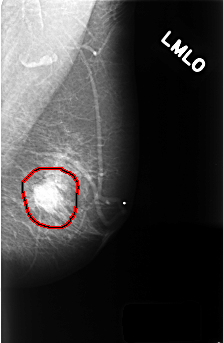

ics_version 1.0 filename C-0360-1 DATE_OF_STUDY 15 5 1997 PATIENT_AGE 59 FILM FILM_TYPE REGULAR DENSITY 2 DATE_DIGITIZED 12 11 1998 DIGITIZER LUMISYS LASER SEQUENCE LEFT_CC LINES 4576 PIXELS_PER_LINE 2896 BITS_PER_PIXEL 12 RESOLUTION 50 OVERLAY LEFT_MLO LINES 4456 PIXELS_PER_LINE 2896 BITS_PER_PIXEL 12 RESOLUTION 50 OVERLAY RIGHT_CC LINES 4560 PIXELS_PER_LINE 2920 BITS_PER_PIXEL 12 RESOLUTION 50 NON_OVERLAY RIGHT_MLO LINES 4576 PIXELS_PER_LINE 2864 BITS_PER_PIXEL 12 RESOLUTION 50 NON_OVERLAY |

FILE: C_0360_1.LEFT_MLO.OVERLAY TOTAL_ABNORMALITIES 1 ABNORMALITY 1 LESION_TYPE MASS SHAPE OVAL MARGINS MICROLOBULATED ASSESSMENT 5 SUBTLETY 5 PATHOLOGY MALIGNANT TOTAL_OUTLINES 1 BOUNDARY |